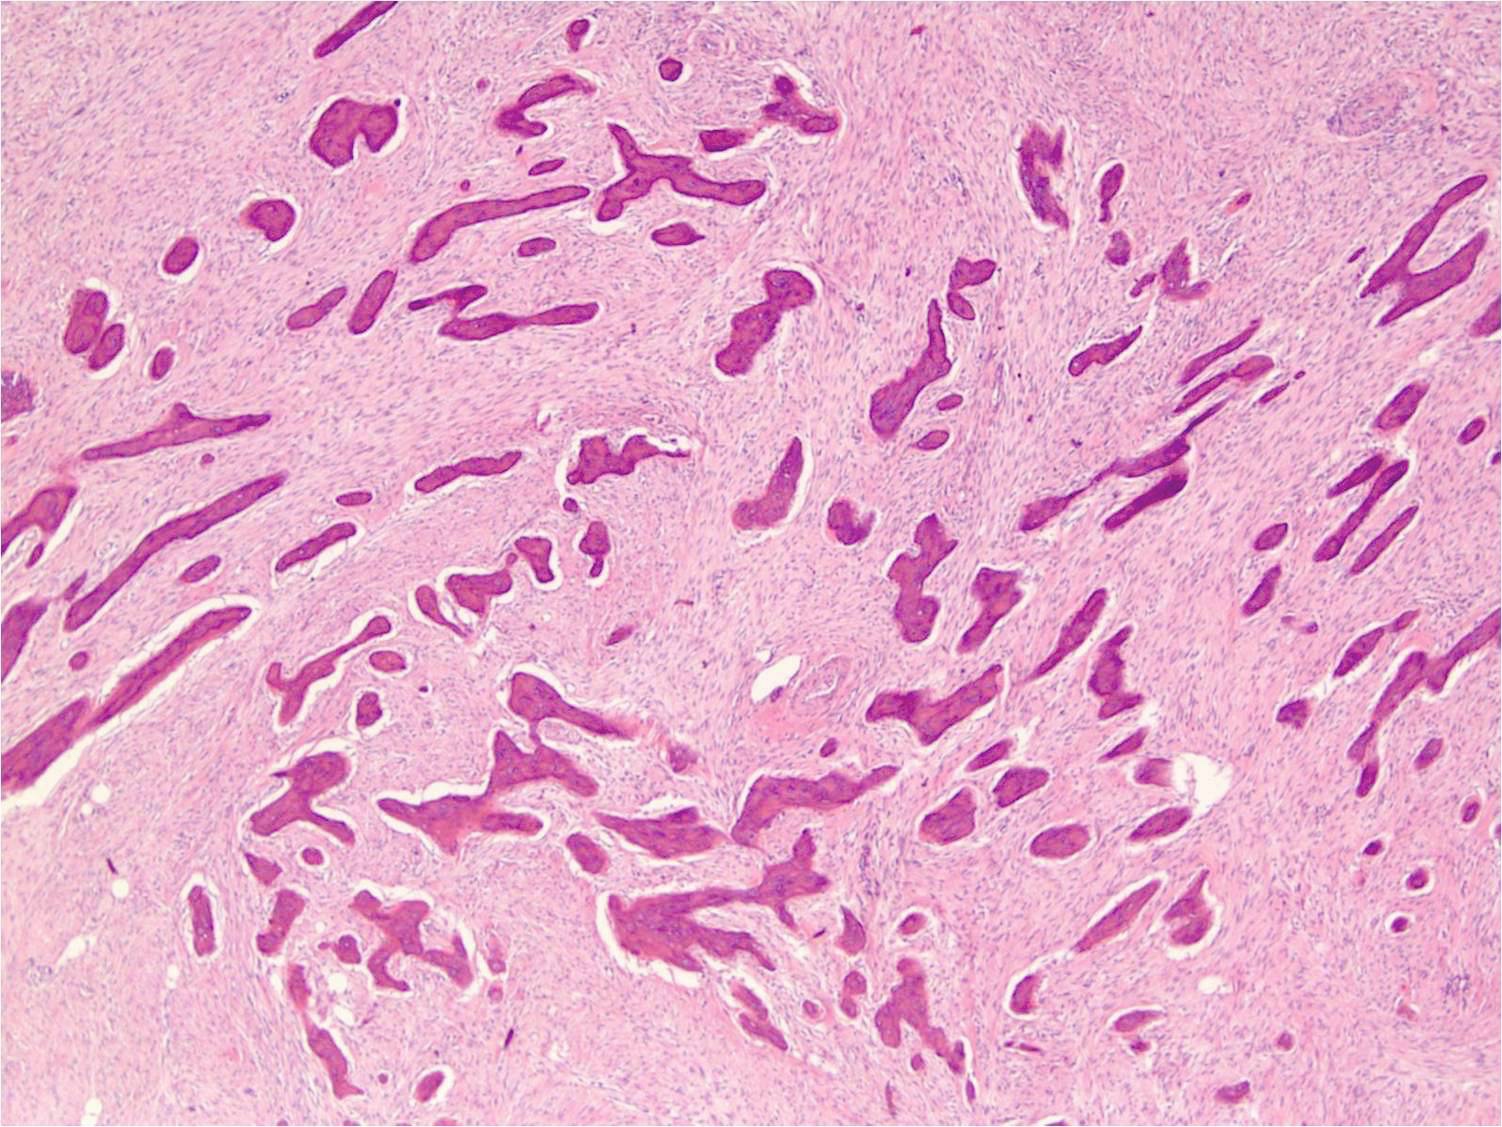

- Periosteal osteosarcoma:

- Ossified mass: intimately attached to native cortex (secondary to endochondral ossification)

- Pericortical bone: dense, mature bone

- Bony spicules: radiate from the dense pericortical bone peripherally and admix with the hyaline cartilage component

- Large vascular cores in center of bony spicules

- Periphery of spicules is calcified / osseous or chondro-osseous and merges with (atypical) hyaline cartilage

- Periphery of mass (majority of the tumor’s volume):

- Atypical hyaline cartilage (appearance of grade 1 - 3 chondrosarcoma); may have myxoid change

- Osseous component (always present but not the dominant component): intermediate grade osteosarcoma intermixed with cartilaginous component; may have lace-like bone but large areas of conventional osteoblastic osteosarcoma are not present

- May have an admixed fibroblastic component (fascicles of mitotically active spindle cells)

- Ossified mass: intimately attached to native cortex (secondary to endochondral ossification)

Microscopic (histologic) images

Contributed by Jesse Hart, D.O., Borislav A. Alexiev, M.D. and AFIP

Practice question #2

A 16 year old boy had a biopsy from a 16 cm mass in the proximal humerus (see image). Which of the following is true?

Practice answer #2

C. Treatment will include neoadjuvant chemotherapy followed by resection. This is a conventional high grade osteosarcoma.